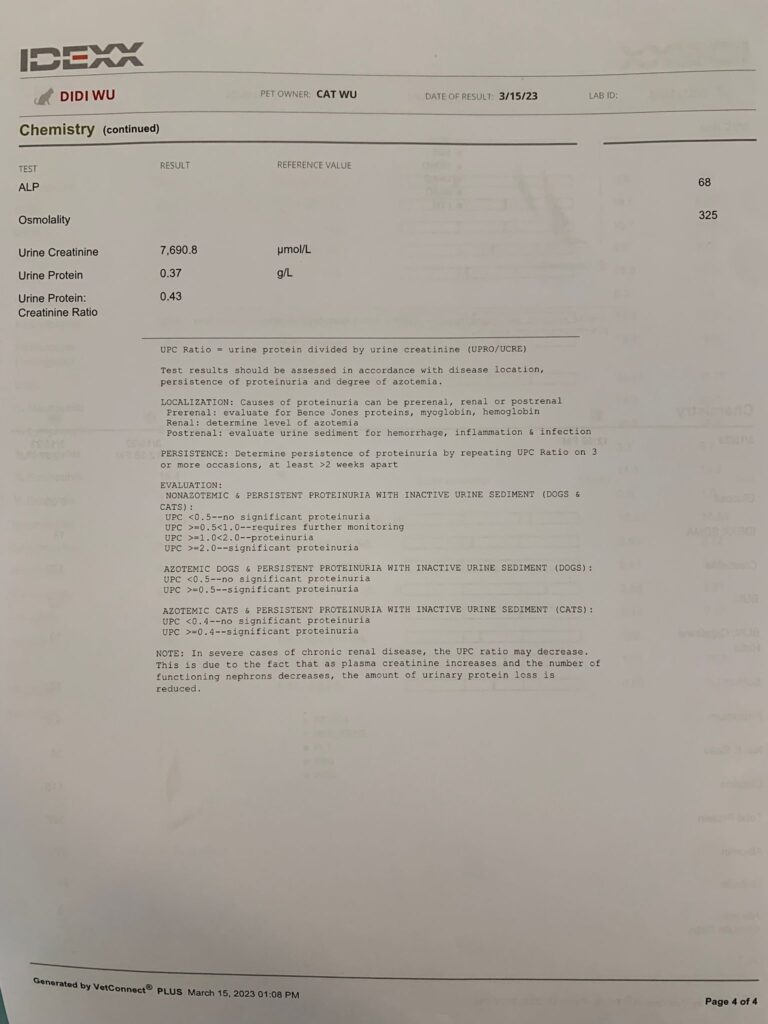

HCT 29.5%, dr nally say she don’t like her EOS 3.24, but it’s a gone down figure cos March he had fenbendazole alr. Will tell them deworm him today. Alt 177 – continue ornipural. GGT 6, restart ursofalk 65mg. 15mg/kg in short. add on Clav 14 days, 0.22ml and anti histamine jabs (expire dec 23) – price $188 don’t make sense so didn’t buy.

Urine taken by cysto, didi not ok w bladder expression.

GGT and UPC back to normal. He say ok for me to stop both urosofalk and semintra (ha I know dr d would say no). recheck 2-4 weeks after stopping. I’ll book review 3 weeks later.

UPC improve to 0.25, but still got to continue ursofalk and semintra. if weight maintain, review in 2 months. If weight drop, review in 1 month. I think didi mouth is the cause of the inflammation leh. but no way I’ll let him do dental.

HCT 29.2%, Erm drop leh. (Semintra loh) – but have to continue (UPC 0.43) and Clav have to continue

Sg 1.014 – Dilute urine, losing a little protein in urine, can try low dose semintra 1mg/kg (nowadays vet give 2mg per kg, n they finally acknowledge that 10-15% become anemic as a side effect)

I trying 0.5mg/ kg and review to make sure rbc stable n upc go down. UPC 0.39